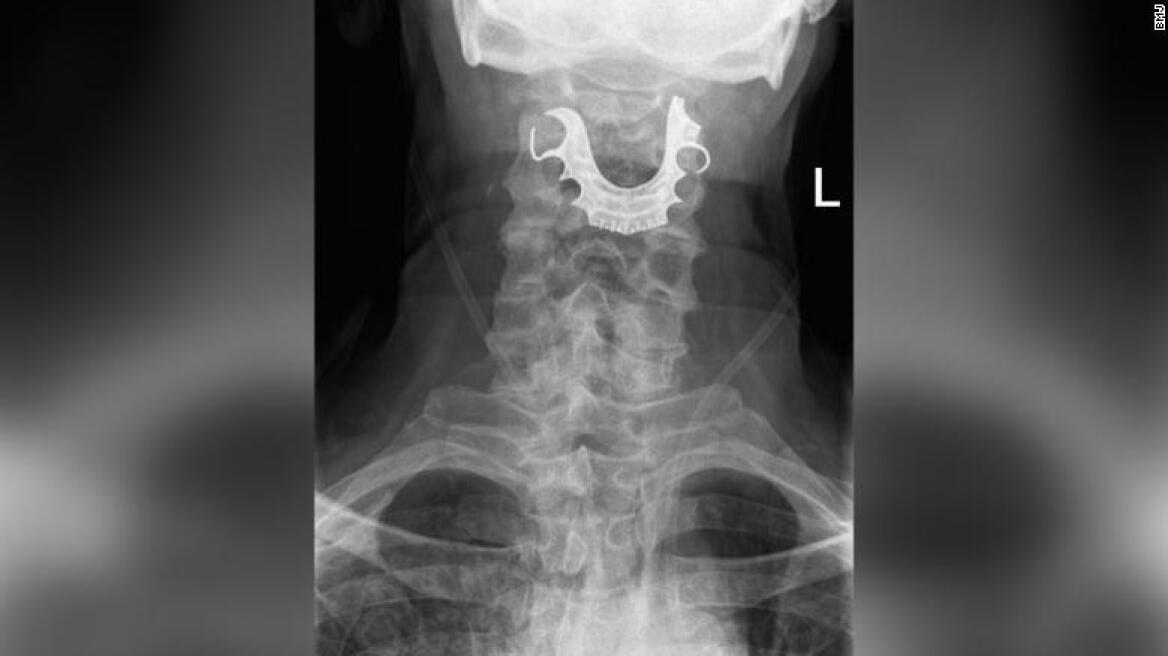

Τελικά, μέσω μιας διαγνωστικής διαδικασίας οι γιατροί εντόπισαν το ημικυκλικό αντικείμενο σφηνωμένο πάνω στις φωνητικές χορδές του άνδρα, που είχε προκαλέσει εσωτερικές φουσκάλες και πρήξιμο.

Ο 72χρονος, που είχε χάσει την μερική οδοντοστοιχία κατά την πρώτη του επίσκεψη στο νοσοκομείο αλλά δεν είχε φανταστεί ότι αυτή βρισκόταν στον... λαιμό του, εισήχθη εσπευσμένα στο χειρουργείο για την αφαίρεση της μερικής οδοντοστοιχίας, που αποτελούνταν από το μεταλλικό πλαίσιο που εφαρμόζει στην οροφή του στόματος και τρία τεχνητά δόντια.